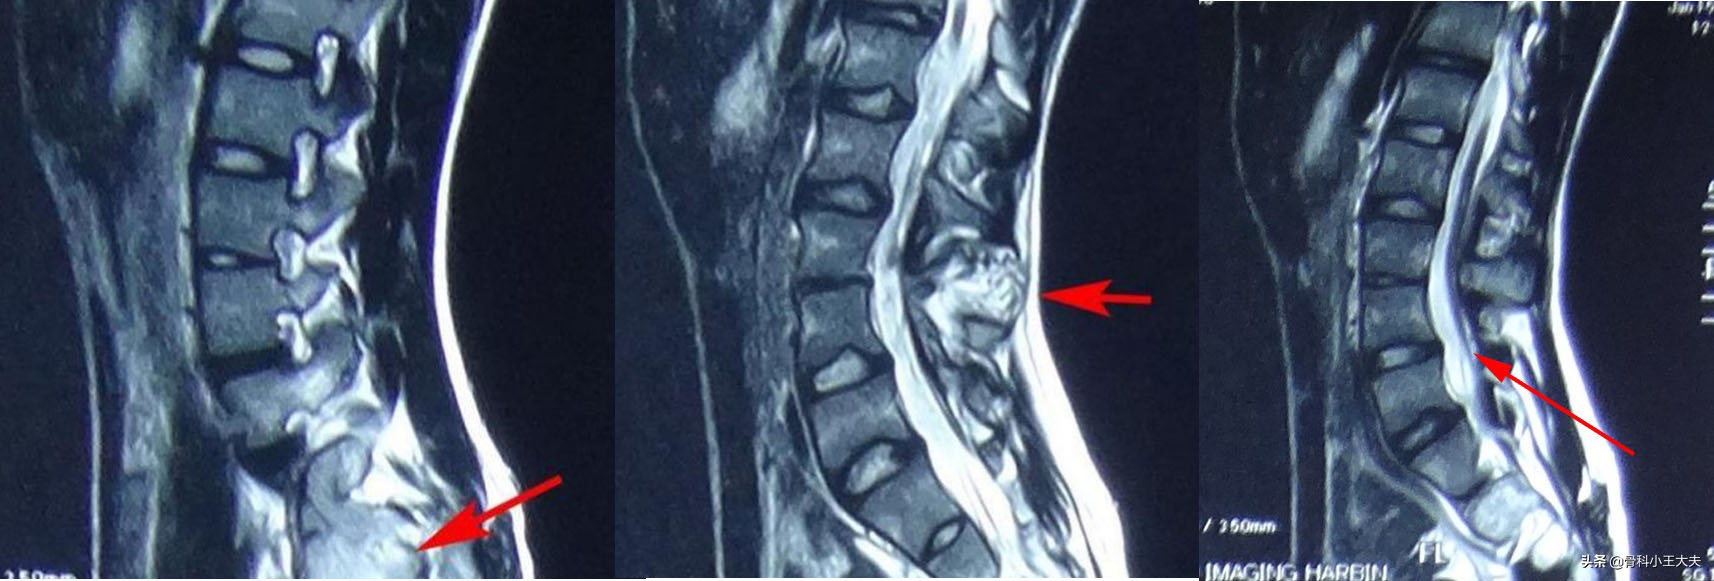

腰椎病变 比如腰椎间盘突出压迫刺激神经根,脊柱结核、肿瘤,腰椎滑脱,脊柱骨折等,这些可引起脊柱姿势改变,产生脊柱侧弯的表现,当把这些原因解决后,脊柱侧弯即可自行矫正。

腰椎病变(比如图示腰椎脊柱结核)同样可引起脊柱侧弯